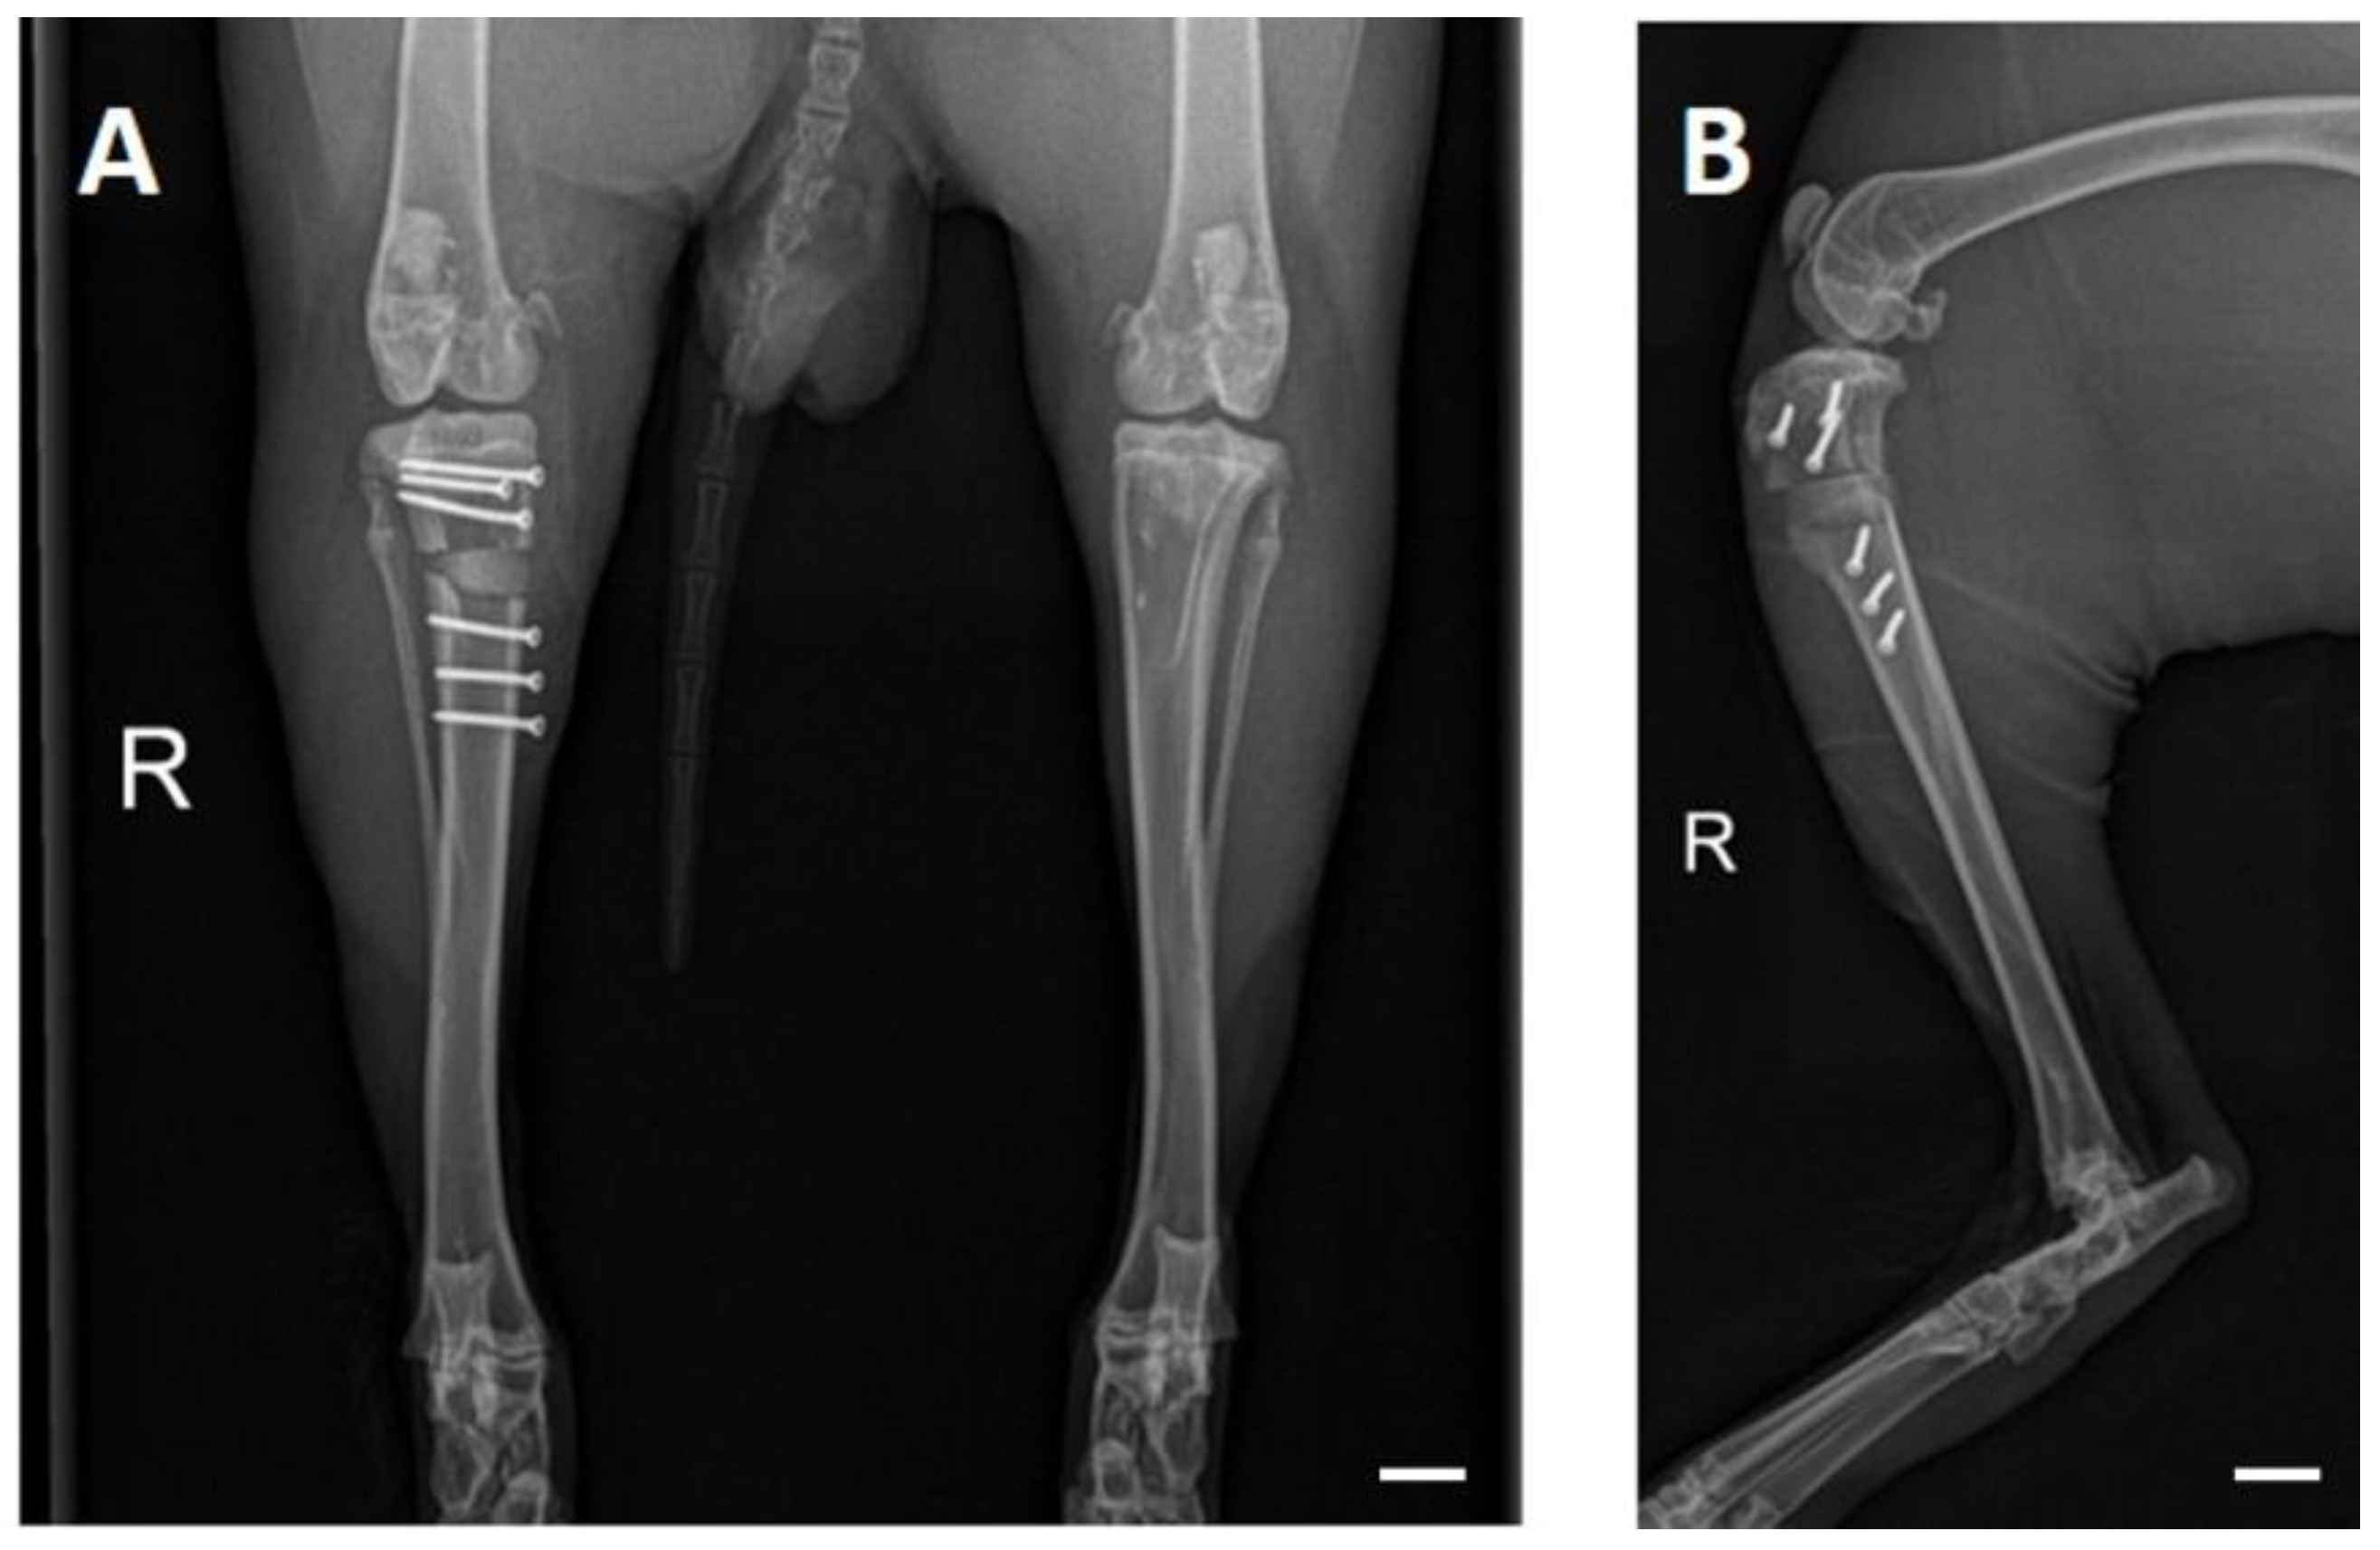

3.3. OP and Clinical Examination

3.4. X-ray Examinations